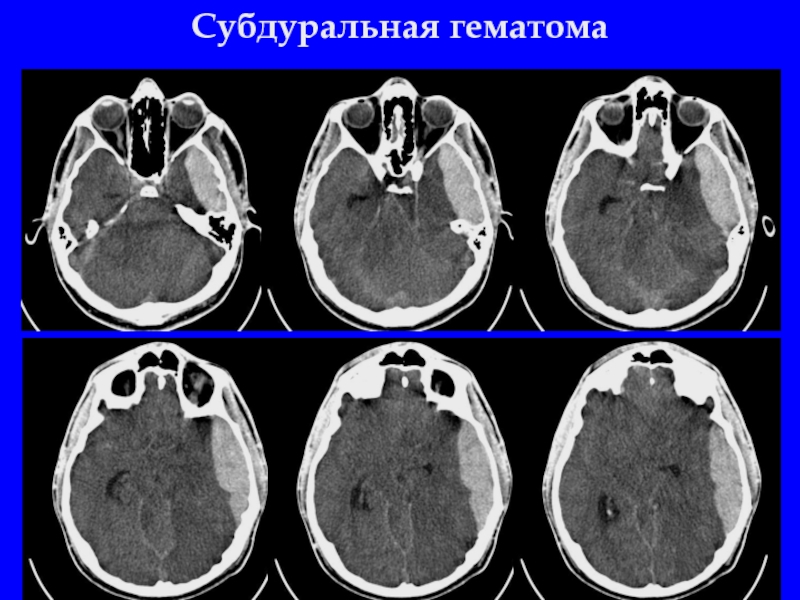

Слайд 15Субдуральная гематома (56-65%) справа. Субарахноидальное кровоизлияние. Латеральная дислокация

Слайд 16Субдуральная гематома. Субарахноидальное кровоизлияние